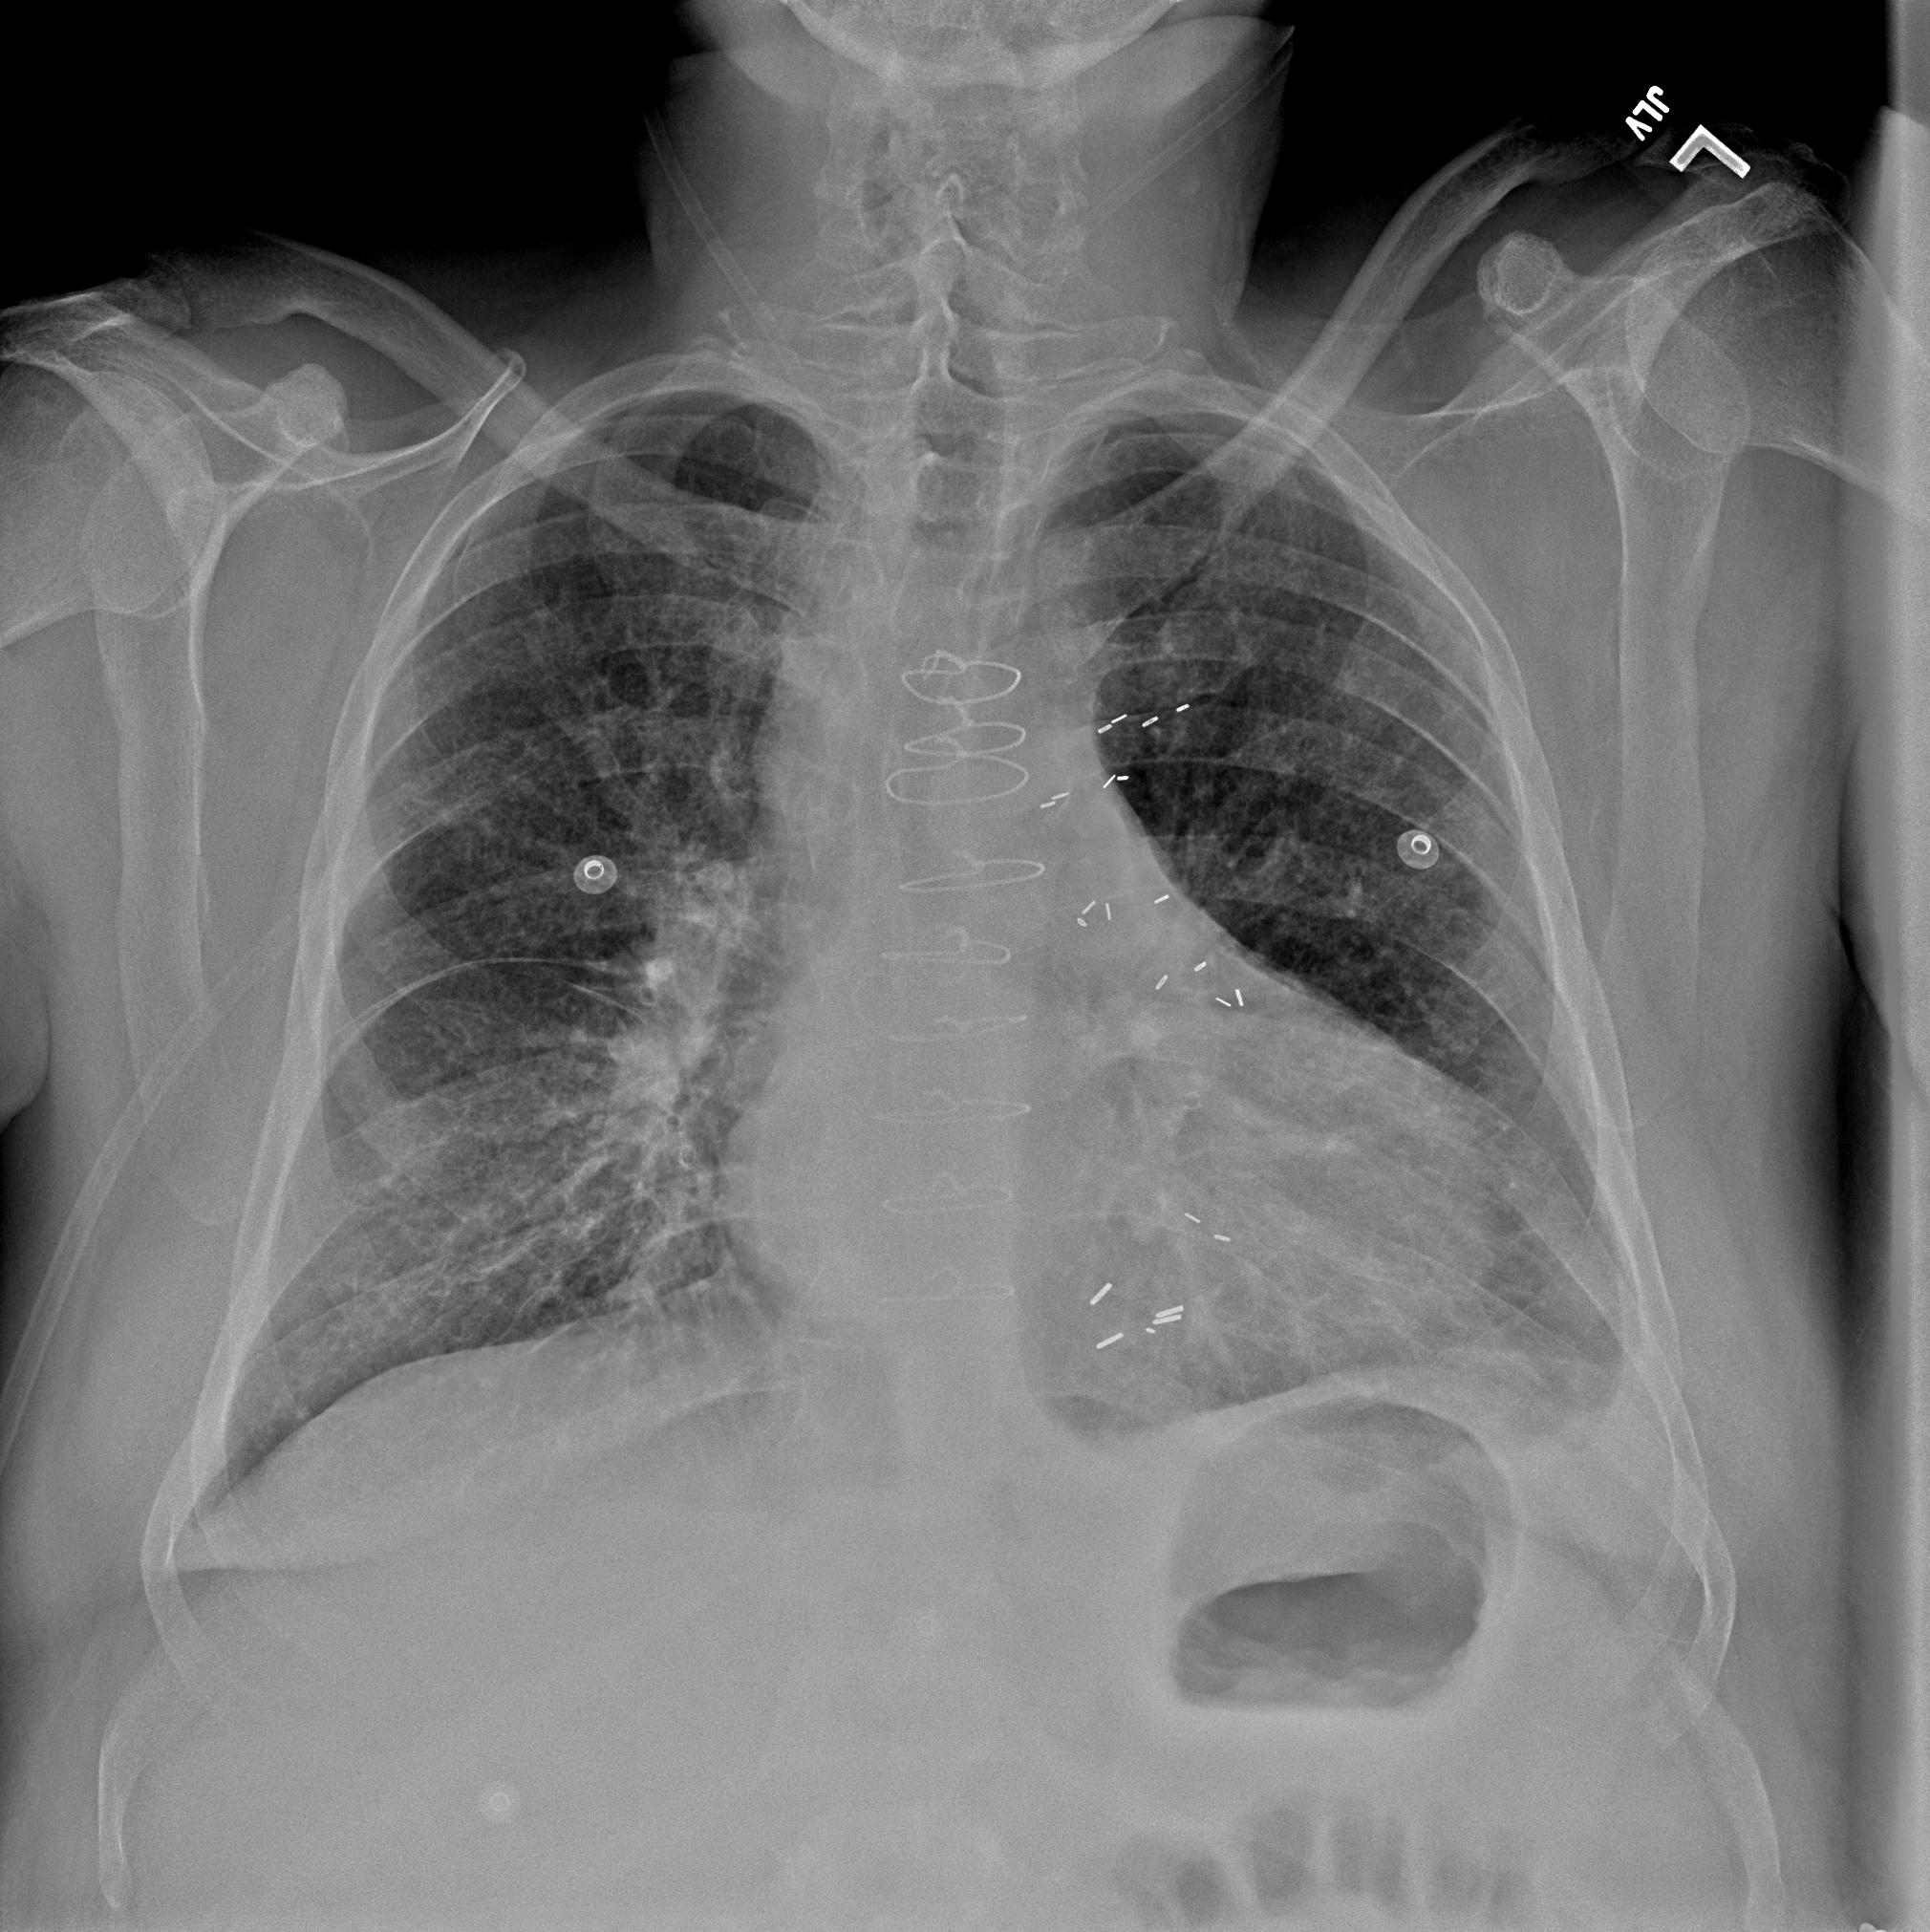

Practice Cases